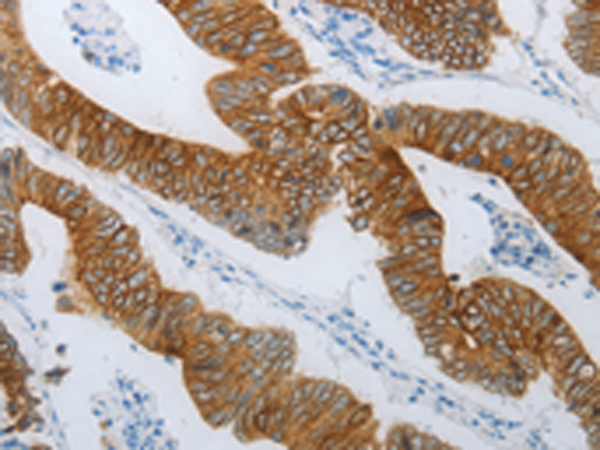

分类: 科研抗体货号: P04438别名: ROS; MCF3; c-ros-1应用: IHC反应种属: Human